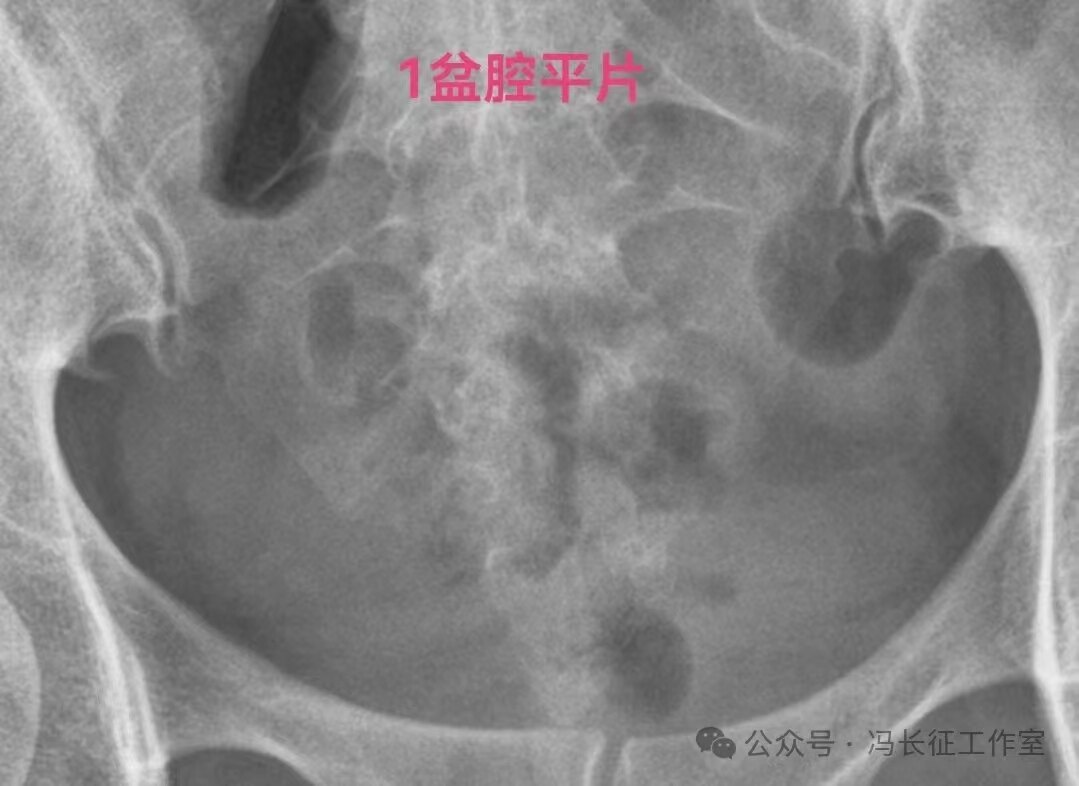

输卵管造影可以通过输卵管柔软度、近端是否和宫腔相通、积水输卵管粘膜情况、是否多囊、是否有造影剂进入盆腔弥散、管壁厚度六个方面对积水输卵管功能进行初步评估。提示输卵管功能好的征象:输卵管走行柔软、近端是否和宫腔相通、输卵管粘膜多,形态大致正常、单囊、弥散相有造影剂进入盆腔、管壁薄。提示输卵管功能受损或丧失的征象:输卵管走行僵硬、近端和宫腔不相通、管腔粘膜少或无、多囊、弥散相没有造影剂进入盆腔、管壁厚。

下面是一例输卵管功能良好的双侧输卵管积水的图片

双侧输卵管输卵管走行较自然柔软,近端和宫腔相通,输卵管粘膜丰富、单囊,双侧输卵管都向中间的子宫聚拢(提示输卵管系膜好),这些都提示双侧输卵管功能良好。虽然伞端没有造影剂进入盆腔弥散,输卵管管壁厚度和周围粘连情况未知;但是,从前面的信息可以初步估计输卵管功能良好。所以就给她做了腹腔镜行积水远端造口手,恢复伞部的拾卵功能,术后自然怀孕生育。